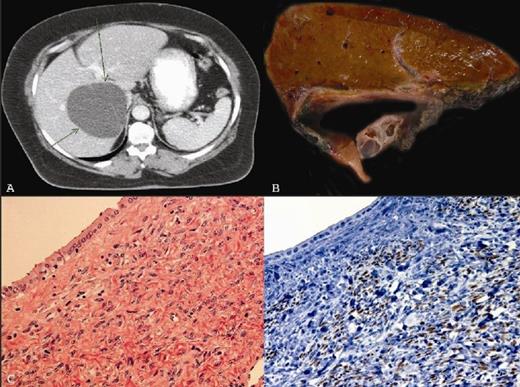

An asymptomatic 60 year-old woman with history of hypertension, diabetes mellitus, arthritis, and echinococcal cyst in the liver which was resected approximately 20 years ago, developed a new liver cystic lesion approximately 7 years after resection. The lesion appeared to slowly increase in size on follow up imaging studies. The patient remained asymptomatic. Contrast enhanced computed tomography (CT) demonstrated a 7.4 x 5.6 x 5.4 cm cystic lesion in the right hepatic lobe with thin septations and no enhancing solid components. Though the serum antibody to Echinococcus was negative, the diagnosis of Echinococcal cyst was made and the patient was started empirically on Echinococcal therapy with Albendazole 400mg daily for 2 months based on her clinical history and imaging findings. Post treatment CT scan showed that the cyst continued to grow (10.5 x 9.1 x 8.2 cm) (Fig. 1A). A partial right lobectomy was performed. Pathologic examination of the 755g resection specimen revealed an 8 x 7 x 5 cm subcapsular multiloculated cyst. The cystic structures ranged from 0.4 cm to 7.2 cm in greatest dimension (Fig. 1B). The cyst contained clear yellow fluid with a smooth inner cyst wall. The uninvolved hepatic parenchyma was grossly unremarkable. Histopathologically, the cysts were lined by mucinous columnar and/or cuboidal epithelium with surrounding subepithelial ovarian-type stroma (Fig. 1C). The ovarian-type stroma was positive for oestrogen receptor (ER) (Fig. 1D), progesterone receptor (PR), and inhibin; while the lining epithelial cells were positive for epithelial membrane antigen (EMA), carcinoembryonic antigen (CEA), and mucicarmine. These are typical features for pathologic diagnosis of mucinous cystic neoplasm of the liver (MCN).

1A) Contrast enhanced computed tomography (CT) demonstrating a cystic lesion in the right hepatic lobe with thin septations. 1B) Partial right lobectomy specimen showing subcapsular multiloculated cyst. 1C) The multiloculated cysts lined by mucinous columnar and/or cuboidal epithelium with surrounding subepithelial ovarian-type stroma (H&E, X 400). 1D) The ovarian-type stroma was positive for oestrogen receptor (Immunohistochemistry, X400)